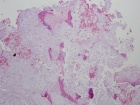

Patient is a 26 y/o male w/ hx. of polyostotic fibrous dysplasia s/p IM nailing for a pathologic L. femur fx. seven yrs. ago presents c/o 1 yr. hx. of increasing L. lat knee pain/swelling; PMH: polyostotic fibrous dysplasia and L. humerus fx; PE: L. knee w/ minimal effusion; +TTP over lat. condyle and w/ flexion to 100 deg; NVI